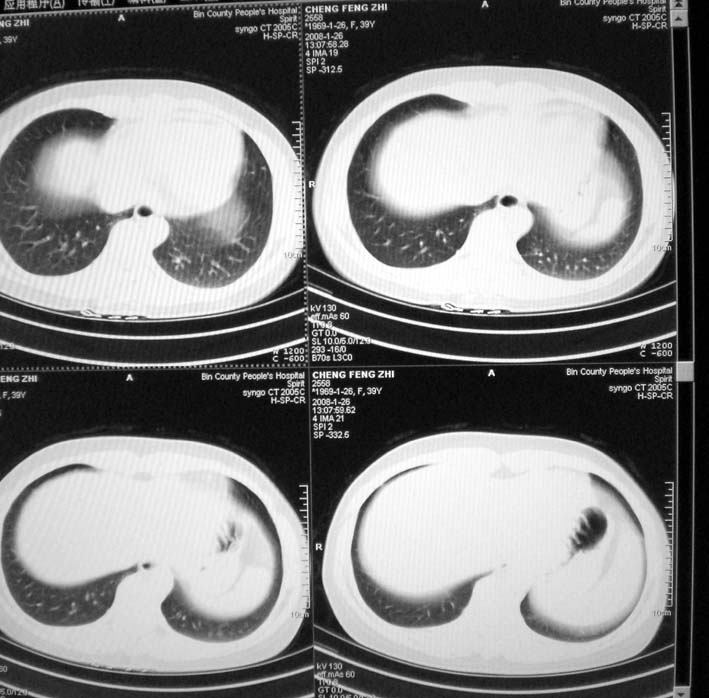

以下是引用guoke在2008-1-27 14:15:00的发言:[br]纵隔增宽,纵隔内血管境界不清,心包积液,考虑纵隔淋巴瘤.[br]

以下是引用随光逐影在2008-1-27 15:52:00的发言:[br]1)考虑为:淋巴瘤。建议:行进一步检查。2)心包积液。